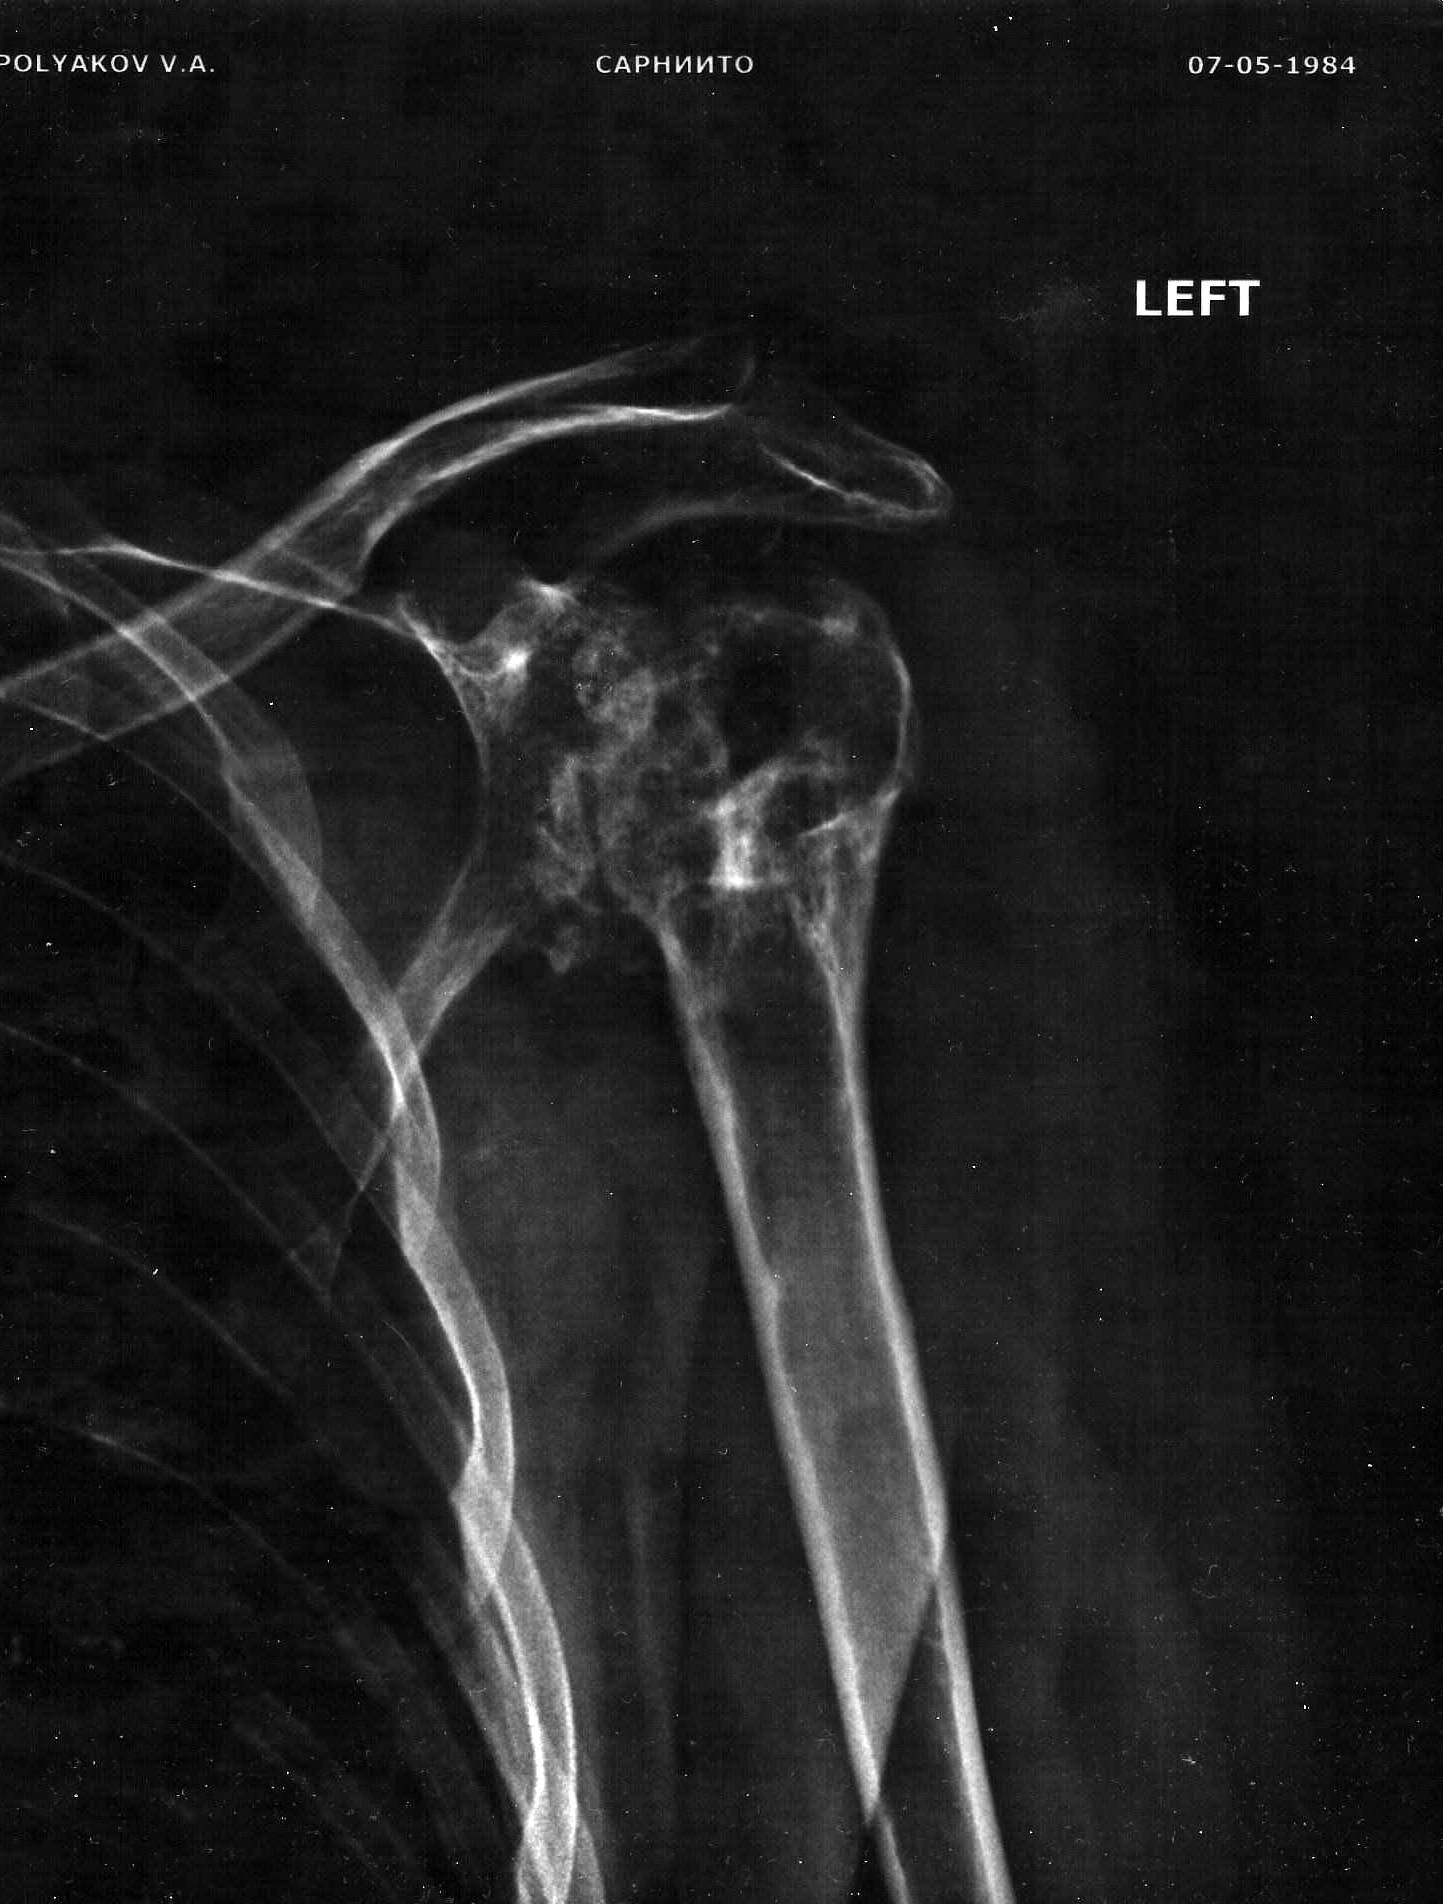

Мужчина 33 года. Травма от 2009 года - размозжение верхней трети плеча.

Заживление вторичное. на протяжении 4 лет проводилось лечение

остеомиелита головки левой плечевой кости с относительно

удовлетворительным эффектом. Однако функция не восстановилась. в

настоящий момент имеется ограничение функции на 50 %, выраженный болевой

синдром без общей островоспалительной реакции. Рентгенография приложена.

По данным КТ имеется: хронический остеомиелит,

дегенеративно-дистрофичекие изменения левого плечевого сустава.